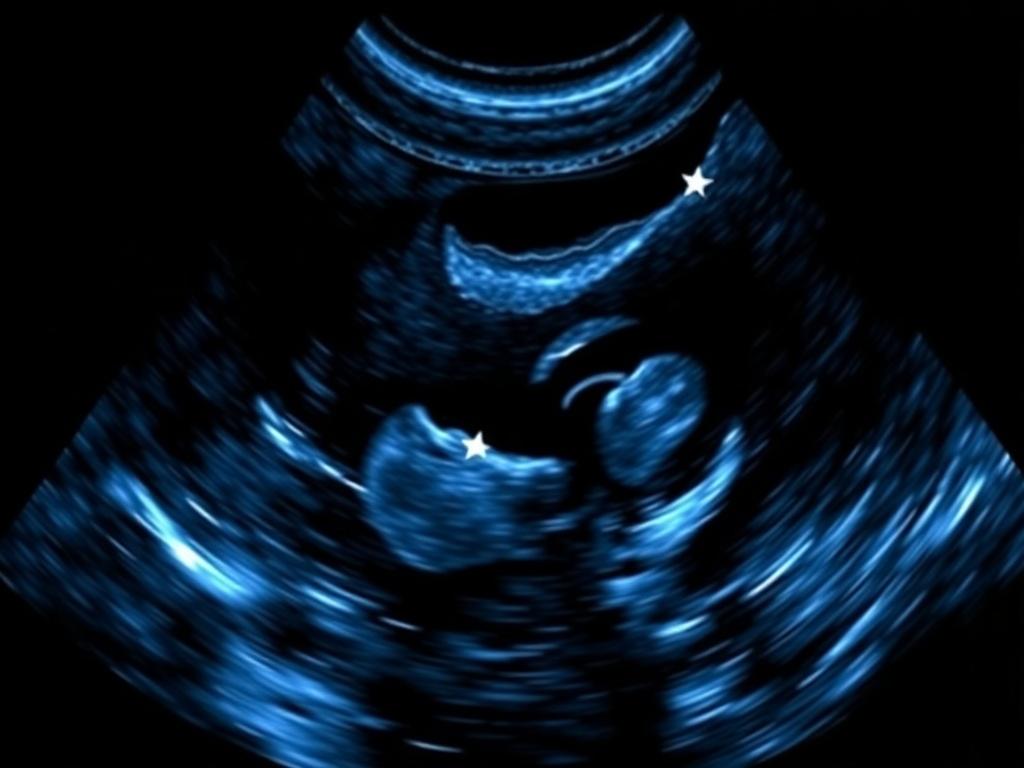

Фармакодопплерография сосудов — это современный метод диагностики, который используется в урологии для оценки кровотока. В отличие от обычного УЗИ, здесь врач получает данные о работе артерий и вен под нагрузкой. Процедура проводится с помощью специального препарата, который вводится путем инъекции в кавернозные тела.

Основная цель — выявить причины нарушения эрекции. Время манипуляции занимает около 30 минут. Сначала делается сканирование в покое, затем после введения вазоактивного средства. Специалисты отслеживают скорость кровотока, приток и отток крови. Это позволяет определить степень поражения сосудов полового члена.

Главный вопрос касается точности получаемых данных. Стандартное сканирование оценивает структуру тканей пациентов в статике. Фармакодопплерография показывает характер крови в движении. Это критически важно для мужчин с функциональными расстройствами.

Оценивается артериальный приток и венозный отток крови. Для исследования полового члена требуется искусственная нагрузка. Без стимуляции видно меньше деталей. Результаты исследования дают полную картину состояния. Патологии полового члена становятся явными только при нагрузке. Заболевания выявляются точнее.

Расшифровка данных требует внимания. Врач оценивает индекс резистентности. Систолическая скорость важна для артерий. Если показатель высокой скорости, это хорошо. Обычно норма выше 30 см/с. Для вен важен отток. Заключение врача основано на цифрах.